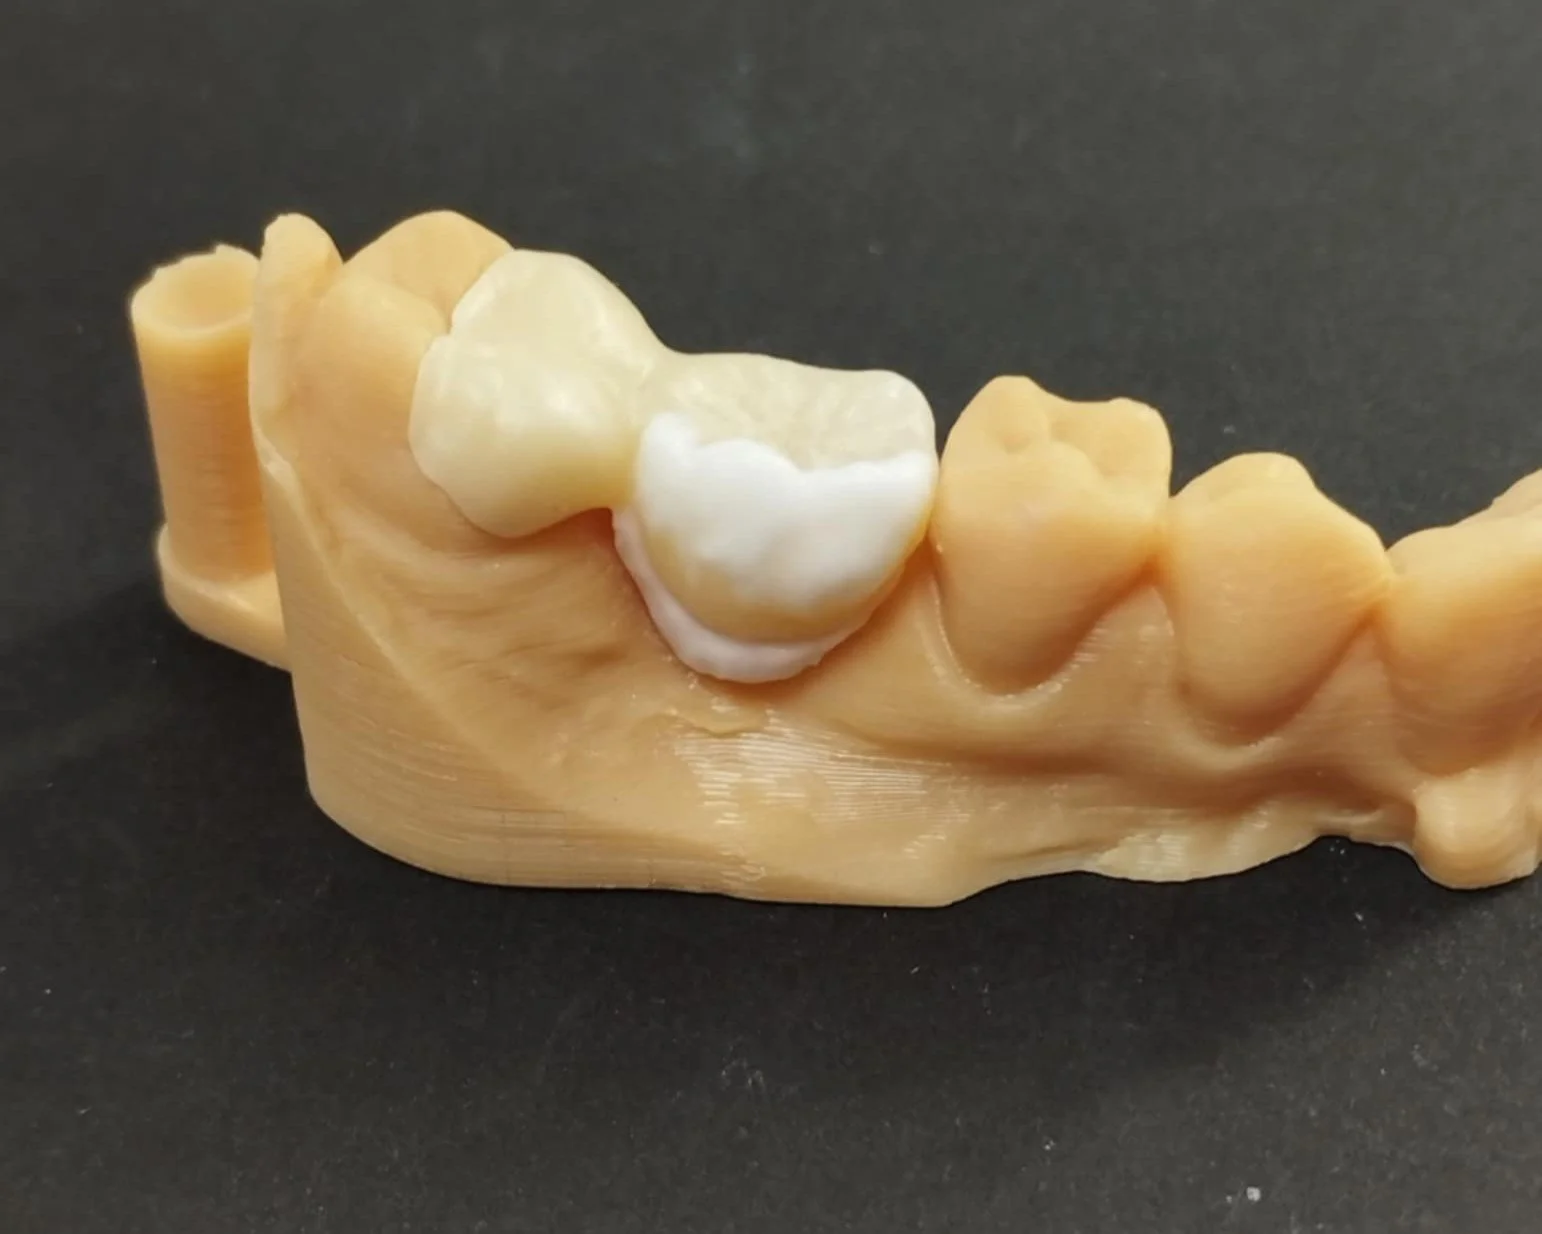

Relativement récents, les bridges collés cantilever postérieurs constituent une alternative fixe, fiable et véritablement minimalement invasive aux implants dans les secteurs postérieurs. Cette thérapeutique qui repose sur des indications bien précises est parfois débattue avec passion sur les réseaux sociaux ou dans les congrès scientifiques. Cependant des études cliniques existent, tout comme des recommandations validées dans des journaux internationaux. Leur succès repose sur des préparations et des principes biomécaniques rigoureux, pourtant simples à intégrer au quotidien. Cette intervention propose un guide clair et opérationnel incluant indications, étapes clés, protocoles d’adhésion et réglages occlusaux pour les mettre en œuvre avec confiance et reproductibilité.